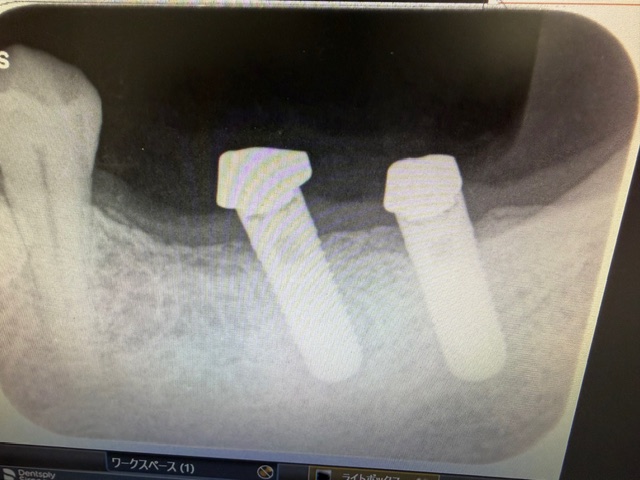

┏67、2本欠損なのですが、インプラント埋入位置はなぜか┏78部で、上部構造体は┏678の逆

カンチレバー形態でした。

噛み合わせの歯牙は長期放置状態のため挺出し、そのためかアバットメントの高さは低いにも関わらず

スクリューリテインではなくセメントでセットされた状態。

このケースのこの部分に限っての最適解は、┏67にインプラント再治療、次策として上部構造をスク

リューリテインとして新しく作り直す、次々策として手前にもう1本インプラントを追加し、力を分散

させるというものでしょうが、患者さんが納得されないので、当院ではセメントでセットして終了しま

した。